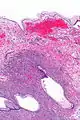

| Micrograph showing a mucinous cystadenoma of the ovary. H&E stain. | |

Mucinous cystadenoma is a benign cystic tumor lined by a mucinous epithelium. It is a type of cystic adenoma (cystadenoma).

Mucinous cystadenomas make up 15–20% of all ovarian tumors. They often become very large and can extend up into the abdomen.

Benign mucinous cystadenomas compose 80% of mucinous ovarian tumors[2] and 20–25% of benign ovarian tumors overall. The peak incidence occurs between 30 and 50 years of age. Benign tumors are bilateral in 5–10% of cases.